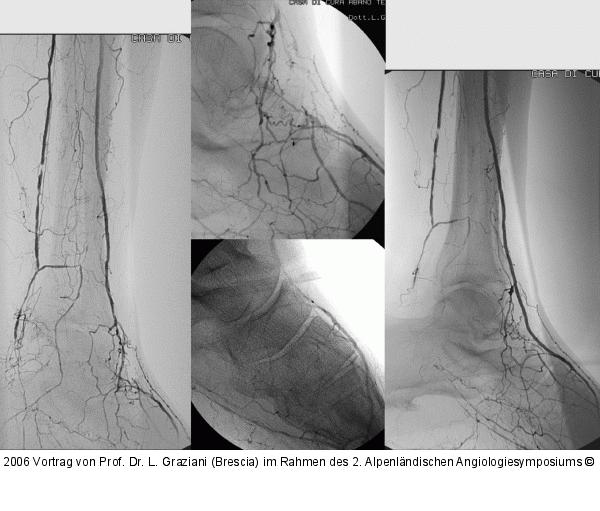

Vortrag von Prof. Dr. L. Graziani (Brescia) im Rahmen des 2. Alpenländischen Angiologiesymposiums

PTA of the foot arteries in diabetics: Extremities Extreme Angioplasty

Abbildung 42: PTA